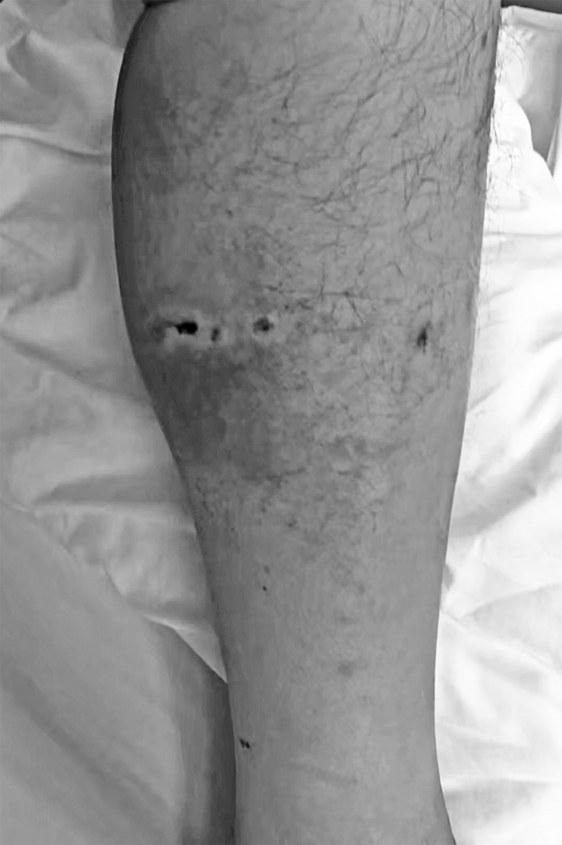

李某小腿被熊咬伤

22日,躺在病床上的李某讲述了自己被黑熊袭击的经过。他称,袭击自己的熊有一两百斤重。当时,自己上山捡菌后在返回途中,刚好与黑熊碰了个正面。黑熊突然发动袭击,咬了他小腿一下,然后一巴掌将其打下山坡。慌乱中,李某的水鞋(雨靴)掉落了一只,黑熊咬着鞋就跑了。“是我穿的水鞋救了自己一命。”李某表示,由于有水鞋的保护,小腿受伤并不严重。李某回忆,山坡下就是山崖,有20多米深。他正好被山坡上的树枝拦住,晕了过去。如果是掉到崖底,可能就没救了。他醒来后找到手机,爬到山梁上,才打通家里的电话。

岭楠村党支部书记陈清斌介绍,李某被送往城口县人民医院治疗,头部和腿部受伤,身上还有多处骨折。目前,李某意识清醒,说话正常,没有生命危险。